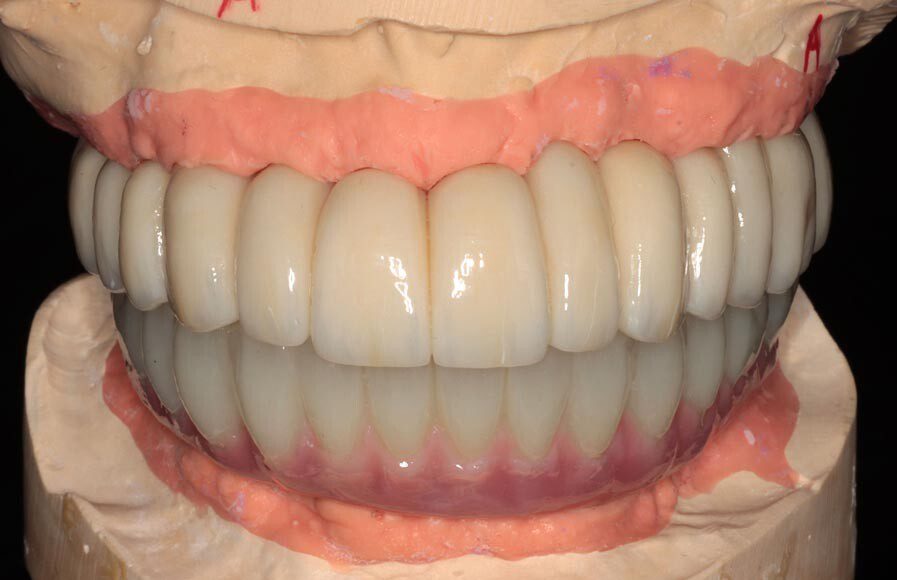

Frontal view of articulated Master Casts. We use the temporary bridges in a procedure called “records” to articulate the Master Casts to the articulator. This gives us the static and dynamic recording of the patient’s mouth and bite.